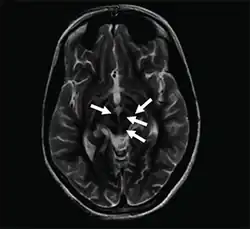

Axial T2-weighted MRI of the brain at the level of the midbrain showing the characteristic ‘face of the giant panda’ sign, with normal red nuclei and substantia nigra (pars reticulata) against a background of hyperintensity in the tegmentum, as well as hypointensity of the superior colliculi

The face of the giant panda sign, panda sign of the midbrain or double-panda sign is a characteristic "panda's face" appearance in magnetic resonance imaging (MRI) images of people with Wilson's disease. Along with Kayser–Fleischer rings, the sign is helpful in diagnosis.[1]

While the sign is most common in Wilson's disease, it has been rarely reported in acute disseminated encephalomyelitis,[2] rabies encephalopathy,[3] toxic leukoencephalopathy[4] and Leigh syndrome.[5]